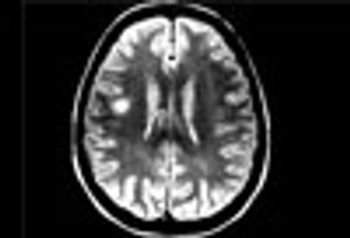

MRI is now central to the diagnosis of multiple sclerosis. Because of the modality’s high sensitivity to inflammation and demyelinating plaques, roughly 90% of all MS diagnoses are now based on MRI findings.

Sodium levels are known to be elevated inside the brain stem, cerebellum, and temporal poles early in the course of MS. This study showed total sodium concentrations to be significantly increased in advanced disease-particularly in normal-appearing brain tissues, concomitant with disability.